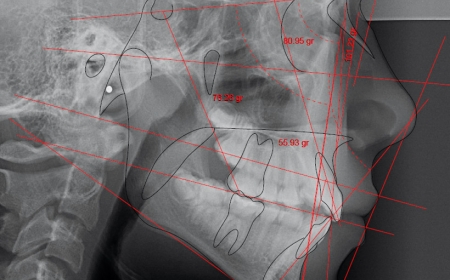

Análises Cefalométricas

exame análises cefalométricas na neox radiologia digital odontologica odontologia uberaba

• Ricketts

• Roth-Jarabak

• Tweed / Steiner